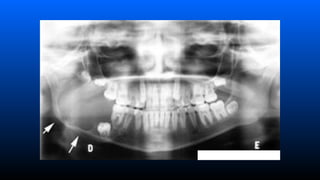

■ Ameloblastoma intra-ósseo

–Aspecto radiográfico

»Lesão radiolucida em forma de bolhas de

sabão multilocular (loculações grandes)

ou favo de mel (loculações pequenas)

associado ou não a um dente incluso;

Tumores Odontogénicos

– Radiología Lesão radiolúcida unilocular ou bolhas de sabão